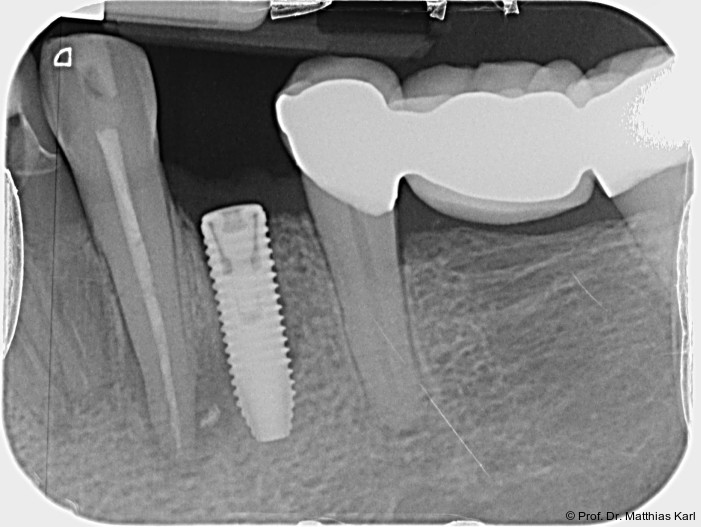

Mikrobewegungen im Verhältnis zum umgebenden Knochenlager. Die Vermeidung solcher Bewegungen ist essenziell, um eine erfolgreiche Osseointegration und damit die Entwicklung einer sekundären, biologisch bedingten Stabilität zu ermöglichen.18 Zur Verkürzung der Behandlungsdauer und zur Ermöglichung einer frühzeitigen prothetischen Versorgung wurden die klassischen operativen Protokolle angepasst. Hierzu zählen die untermaßige Implantatbettpräparation7 sowie der Einsatz konischer Implantatkörper21 (Abb. 1a–2b) mit ausgeprägt aggressiver Gewindegeometrie.8, 14 Beide Maßnahmen führen zu einer erhöhten Kompression des Alveolarknochens, insbesondere in den kortikalen Anteilen.11, 22

Zur Reduktion der Knochenkompression, insbesondere der bukkal gelegenen Lamelle (Abb. 3), werden derzeit Implantate mit dreieckigem Querschnitt10, 12 sowie Implantate mit zervikal reduziertem Durchmesser16 angeboten. Diese scheinen jedoch im Gegensatz zur subkrestalen Positionierung (Abb. 4a–c) von Implantaten23 keine signifikanten Vorteile zu bieten. Bohrprotokolle, welche sowohl auf das jeweilige Implantatsystem als auch auf die vorliegende Knochenqualität abgestimmt sind, haben ebenfalls das Ziel, zu hohe Einbringdrehmomente zu vermeiden.